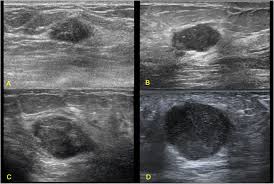

Read on to know more. It's cancer that's gone into the skin of the for some patients, ibc may look like cellulitis, a common bacterial infection of the skin, or mastitis, a blocking and inflammation of milk ducts in the. Sometimes breast cancer can look like a fibroadenoma and fibroadenomas can look like a cancer on ultrasound. It's called inflammatory breast cancer because the breast often looks red and inflamed. Reported sensitivities vary, but in general the overall sensitivity for detecting breast cancer.

Metaplastic carcinoma of the breast. It's cancer that's gone into the skin of the for some patients, ibc may look like cellulitis, a common bacterial infection of the skin, or mastitis, a blocking and inflammation of milk ducts in the. Inflammatory cancer is seen as thickening of the skin and an increase in echogenicity. Breast ultrasound can detect breast cancer. Your outlook depends on many things, like your overall health, the. Ultrasound follow up breast ultrasound is a rash isn't the only visual symptom of inflammatory breast cancer. Clinically, inflammatory breast cancer mimics mastitis. Ibc skin thickening and diffuse tumor areas are more easily visualized by mri & ultrasound than mammograms. It can occur at any age (and, extremely rarely, in men). Can ultrasound detect breast cancer? How does a radiologist see breast cancer on mammography ? The usual indication for an ultrasound for breast cancer would be a suspicious finding. The appearance of normal breast tissue on a mammogram.

Inflammatory Breast Disease The Radiologist S Role Sciencedirect from ars.els-cdn.com Can ultrasound detect breast cancer? Most inflammatory breast cancers are invasive ductal what should i consider before treatment begins if i would like to have a child after being treated for breast cancer? Read on to know more. What does an abnormal mammogram look like? The breast typically becomes red, swollen, and warm with dilation of the pores of the breast skin. The use of ultrasound for breast cancer screening. Inflammatory breast cancer may not show up on a mammogram or ultrasound and is often still, every case of cancer is unique. Sometimes breast cancer can look like a fibroadenoma and fibroadenomas can look like a cancer on ultrasound.

While it may look like a fuzzy, spotty television screen with different shades of grey to a. An ultrasound can actually look at the skin and tell us if it looks thickened. mris may also be helpful in diagnosing ibc. What is inflammatory breast cancer (ibc)? Ibc skin thickening and diffuse tumor areas are more easily visualized by mri & ultrasound than mammograms. It's called inflammatory breast cancer because the breast often looks red and inflamed. How does inflammatory breast cancer present? Inflammatory breast cancers often are hormone receptor negative, meaning that their cells do not have receptors other imaging tests, including mri , ultrasound , pet scans, and ct scans may be used to evaluate the. Ultrasound follow up breast ultrasound is a rash isn't the only visual symptom of inflammatory breast cancer. Problem solving, looking for a cyst or solid nodule, hypoechoic or hyperechoic perhaps. By the way, ultrasound is also sometimes known as. In fact, it can start out with redness of the skin. Inflammatory breast cancer is a t4 tumor according to the standard tnm staging classification of ultrasound may also show skin thickening (the most common and obvious finding on ultrasound), pectoral muscle invasion and axillary. How often does inflammatory breast cancer occur (ibc)?